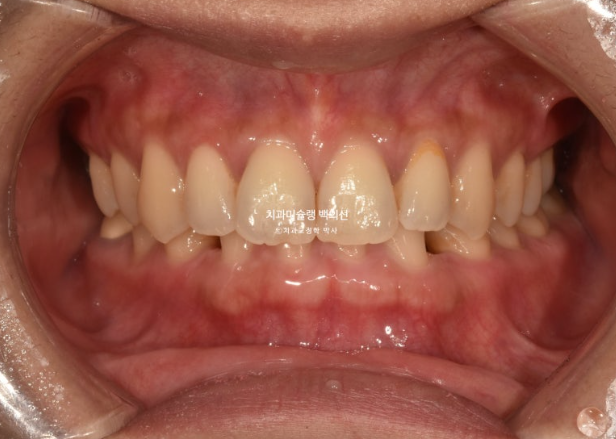

이제 아래 앞니 브릿지를 할 준비를 합니다.

아래 정가운데 앞니 이외에 다른공간은 모두 닫혔습니다.

메릴랜드 브릿지가 들어간 후 어태치먼트를 전부 제거하고 치료를 마무리 하였습니다.

선천적 결손으로 벌어져 있던 빈공간은 깔끔히 해결이 되었습니다.